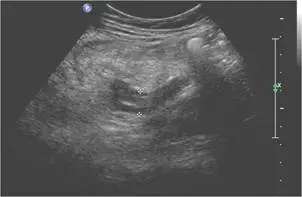

46歲女性病人主訴於月經過後下腹部疼痛,尤其右下腹部疼痛約3天,身體診察右下腹部有壓痛現象,右下腹部超音波檢查如圖,最可能的診斷為何?

- 第一張為右下腹部灰階超音波縱切面,可見一條盲端管狀構造(闌尾),其內外壁清晰,壁層增厚,外徑超過6–7 mm,呈現「target sign」(中心回聲強、外側低迴聲)格局(pmc.ncbi.nlm.nih.gov)。

以上影像符合急性闌尾炎的主要超音波徵象:盲端非蠕動管狀結構、外徑≥7 mm、壁層厚化及周圍炎性回聲增高,並有彩色多普勒顯示之局部高血流。